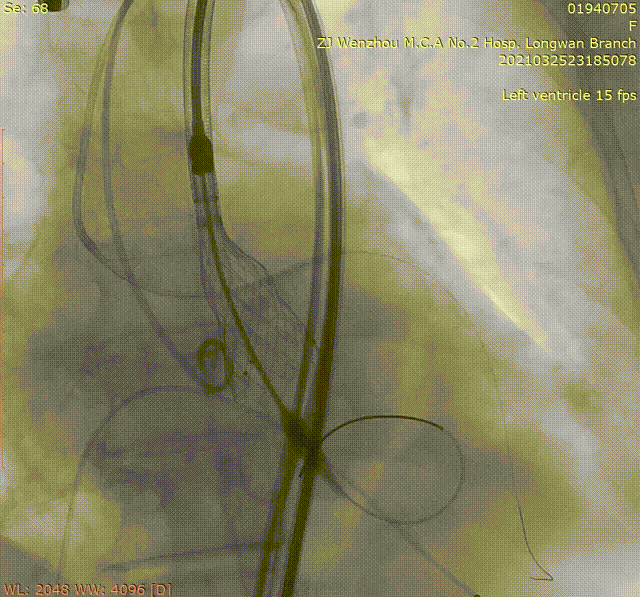

选择20 mm球囊进行预扩,造影提示腰征不明显,存在瓣周漏。瓣叶被掀至STJ,结合术前评估考虑存在冠脉风险,在6F指引导管辅助送入Guidzilla导管实施冠脉保护。选择植入VenusA-Plus® L23型号瓣膜。

主动脉根部造影

20 mm球囊预扩